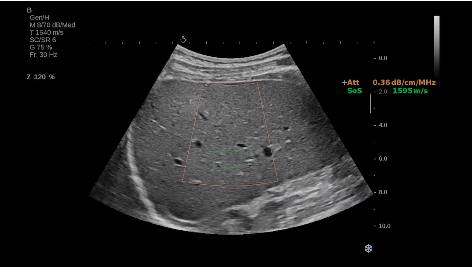

法國聲科影像(SuperSonic Imagine,SSI. Euroniex:FR0010526814)近日發(fā)表公告,宣布其研發(fā)的新一代“極速”超聲成像平臺(UltraFast Imaging),首次實現(xiàn)了肝臟的多項超聲定量評估新指標同步檢測,包括:Att PLUS,SSp PLUS和Vi PLUS等,基本涵蓋肝臟相關(guān)病理變化指征的如纖維化、脂肪變、炎癥等。據(jù)悉,此多項新技術(shù)新將搭載于新Aixplorer系列E超系統(tǒng)。

E超相關(guān)技術(shù)已被多項多中心大樣本研究證實對于肝纖維化無創(chuàng)評估有重要意義,同時也可全面應(yīng)用于乳腺、甲狀腺、肝臟、前列腺、肌骨、婦科等全身各組織器官的定量評估和鑒別診斷。在慢性肝臟方面,聲科E超的肝臟相關(guān)定量診斷技術(shù)集,于2018年獲得美國FDA認證,成為FDA歷史上首次獲批的單病種超聲全面定量解決方案。